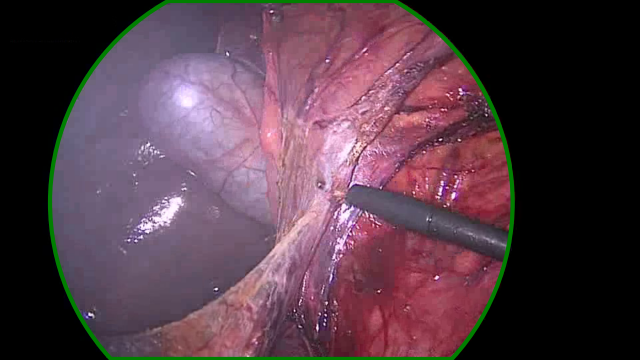

Refer to caption

(a) The dark right-hand side of the content area is missed by both variants. The learned variant gets a slightly better fit, this could be due to a better positioing of points on the left-hand side of the content area.

(b) A noisy and bright border poses a challenge for the handcrafted variant. Too few edge points are detected to make a confident estimate of the circle. The learned variant manages to correctly identify the right-hand edge of the content area, however, the circle fits to incorrect edge points found on the blacked out secondary video feed in the top-left.

(c) Both variants correctly identify the edge in the bottom-left but mistake dark regions in the top-right and bottom-right corners as border regions. The learned variant rejects the final circle as the circle score is too low. This scenario, where a single corner of the image is outside the content area, features prominantly in our failure cases.

(d) In this sample, the handcrafted variant detects edge points in the bottom-left, but scores them poorly. The circle fitting then chooses the incorrectly identified edge points in the top-left. The learned variant scores the detected points in the bottom-left higher, and so the circle fitting finds a satisfying result.

Figure 6: A selection of failure cases of our algorithm taken from the RobustECA dataset, the results of both the handcrafted (left) and learned (right) variants are shown for each image. The edge of the ground truth and inferred circular image projections are shown in blue, and green, respectively. Points indicate the position of detected edge points, the colour of each point indicates its score, going from red to green as the score increases. The vector found when calculating the Hausdorff distance is shown in yellow.